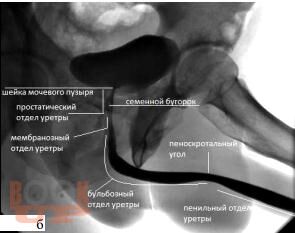

В учебном пособии рассматриваются вопросы, посвященные этиологии, патогенезу и современным методам диагностики стриктурной болезни уретры, а также содержится информация о выборе тактики и способах лечения данной патологии.